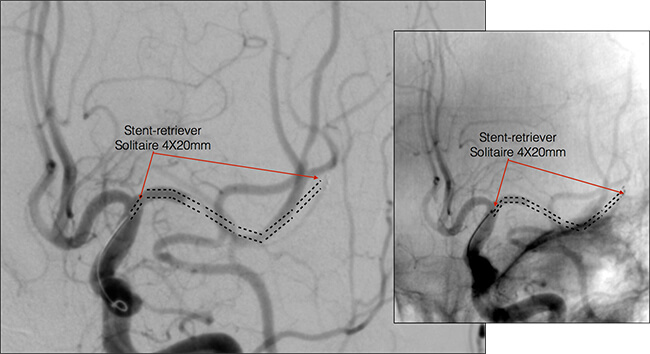

Μέσα από τον μικροκαθετήρα προωθούμε το σύστημα της μηχανικής θρομβεκτομής, το stent-retriever. Μόλις το stent-retriever φθάσει στο άκρο του μικροκαθετήρα, με αργές κινήσεις αποσύρουμε τον μικροκαθετήρα ενώ ταυτόχρονα προωθούμε το stent-retriever το οποίο προοδευτικά εκπτύσσεται μέσα στο αποφραγμένο αγγείο. Το stent-retriever πρέπει να εκπτυχθεί κατά μήκος του αποφράσσοντος θρόμβου.

Περιμένουμε 5 λεπτά ώστε το πλέγμα του stent-retriever να βυθιστεί μέσα στον θρόμβο και το stent-retriever να αλληλεπιδράσει και να εκπτυχθεί σε όλο το μήκος του θρόμβου. Στην διάρκεια αυτή κάνουμε μία έγχυση από τον οδηγό καθετήρα γιά δούμε εάν έχει αποκατασταθεί η ροή μέσα στο αποφραγμένο αγγείο. Αυτό συμβαίνει όταν ο θρόμβος έχει απωθηθεί από το stent-retriever και έχει δημιουργηθεί βατός αυλός κατά μήκος της αποφράξεως.

Όταν δούμε αυτή την εικόνα της πρώτης επανασηραγγοποίησης, αυτό είναι καλό προγνωστικό σημείο γιά την συνέχεια και αποτελεί ένδειξη γιά επιτυχή αφαίρεση του θρόμβου στην συνέχεια.